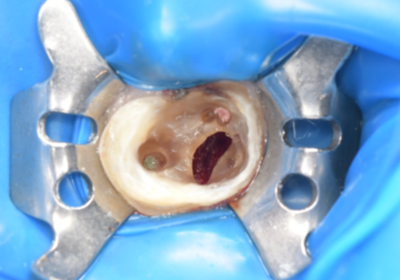

初診時デンタルX線写真

初診時デンタルX線写真とCT画像。

根管外に不透過像とそれを取り囲む透過像を認める。

コアを除去すると、分岐部へつながるパーフォレーションを認めた。

これが排膿の原因であったため、保存は困難と判断した。